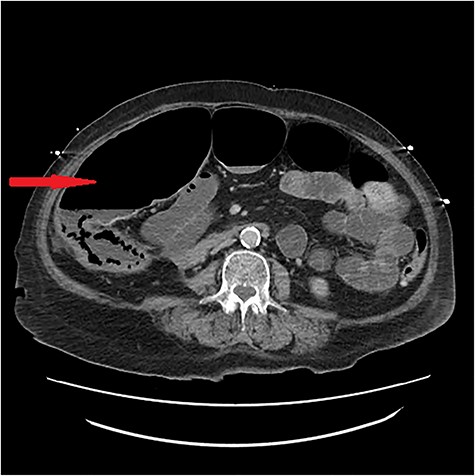

Lumbar puncture on admission was refused but done on Day 4 showing herpes simplex virus 1 infection and acyclovir commenced. On Day 13, an ultrasound for nonspecific abdominal pain showed cholelithiasis without cholecystitis and conservative treatment continued. Pain localized to the right iliac fossa over the next days; CT abdomen pelvis showed ischemia and pneumatosis (Figs. 1 and 2). The laparotomy on Day 18 confirmed bowel ischemia with retrocaecal perforation caused by a terminal ileal band that resulted in internal herniation and gangrene. An extended right hemicolectomy was done. As she was on the maximum dose of inotropes, the abdominal wall was kept open with a Bogota bag for re-look surgery in 24 hours. No progression of ischemia was noted subsequently and the stabilized patient had an ileostomy formed with closure of abdomen.

In our hospital, an arterial phase CT abdomen pelvis is gold standard and our patient’s scan showed acute bowel ischemia of the terminal ileum and ascending colon with pneumatosis (Figs. 1 and 2). The cause was suspected hypoperfusion due to the course of her illness and long intensive care unit stay but a mechanical cause was found on laparotomy, a terminal ileal band that precipitated internal herniation and subsequent compromise of bowel resulting in gangrene and retrocaecal perforation.